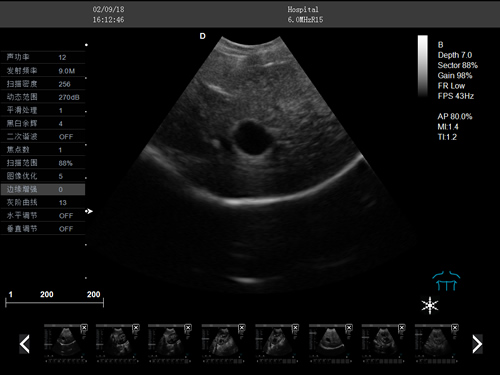

·支持彩色多普勒、頻譜多普勒、能量多普勒等成像技術

·組織諧波成像技術

·中小動物的肝、膽,脾、腎、膀胱、子宮、妊娠等各組織器官的檢查和病變的診斷